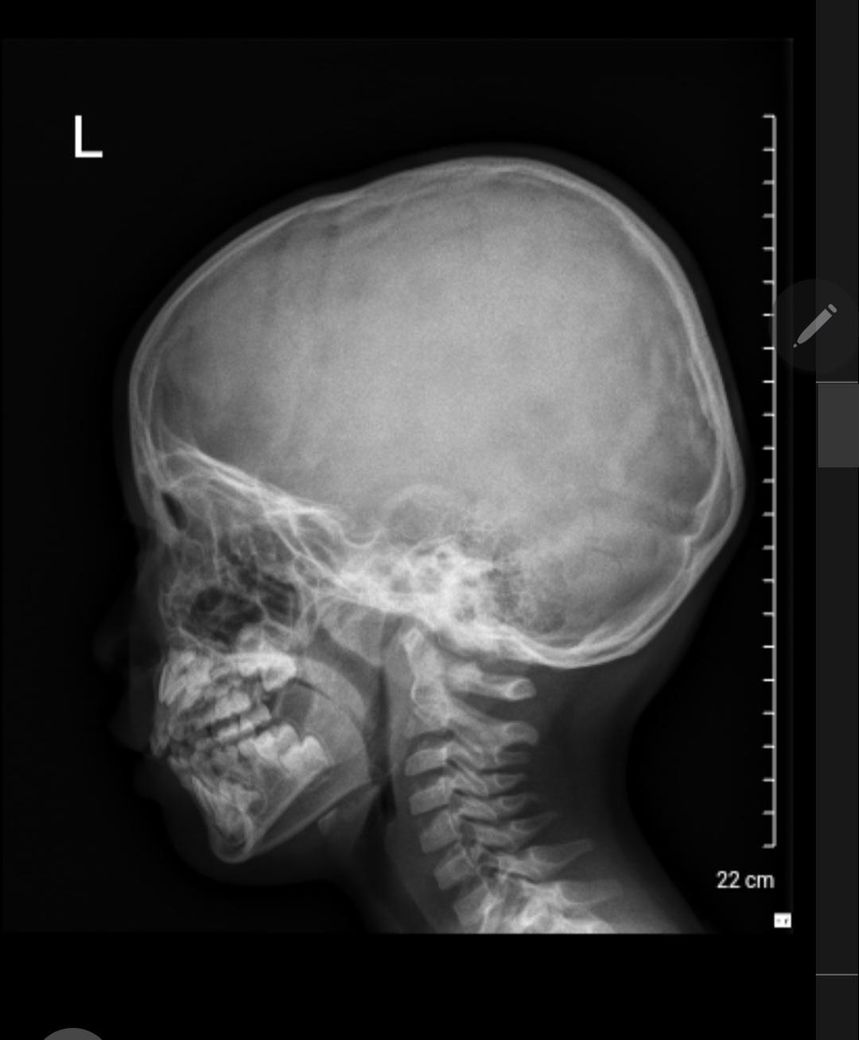

해외에서 엑스레이를 찍었는데 부비동염인가요?

만5세 아이가 자꾸 훌쩍여서 엑스레이를 찍었는데 부비동이 하얗게 보이기는하는데 큰 이상이 없고 비염일 가능성이 커서 약을 먹을 필요가 없고 지켜보라고 했어요. 한국에서 부비동염으로 몇번 고생했어서 혹시 약을 먹어야하는 수준에 부비동염인지 걱정이 되는데 한번 확인 해주실 수 있으실까요?

올려주신 엑스레이에서 부비동염을 의심할 수 있는 소견은 저명하지 않습니다.

먼저 비염에 준한 치료를 받으며 경과를 지켜 보시기 바랍니다.

부비동을 관찰하기에 부적절하게 X-ray가 찍혀있습니다.

고개를 앞으로 숙이고 찍었는데 아래 사진처럼 고개를 위로 들고 X-ray를 찍어야 부비동이 잘 보입니다.

아래 사진에 보면 오른쪽 부비동 (사진상으로는 왼쪽)에 공기가 반정도, 농이 반정도 차있는걸 볼 수 있고 반대쪽에는 검정색 공기가 전혀 없고 농으로 완전히 차있는걸 볼 수 있스빈다.

올려주신 사진에는 잘 보이지 않지만 부비동에 문제 없어 보입니다.